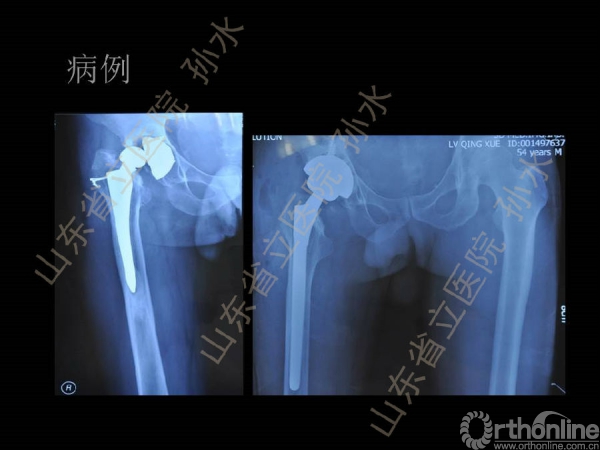

孙水:Jumbo-Cup在髋关节翻修中的应用